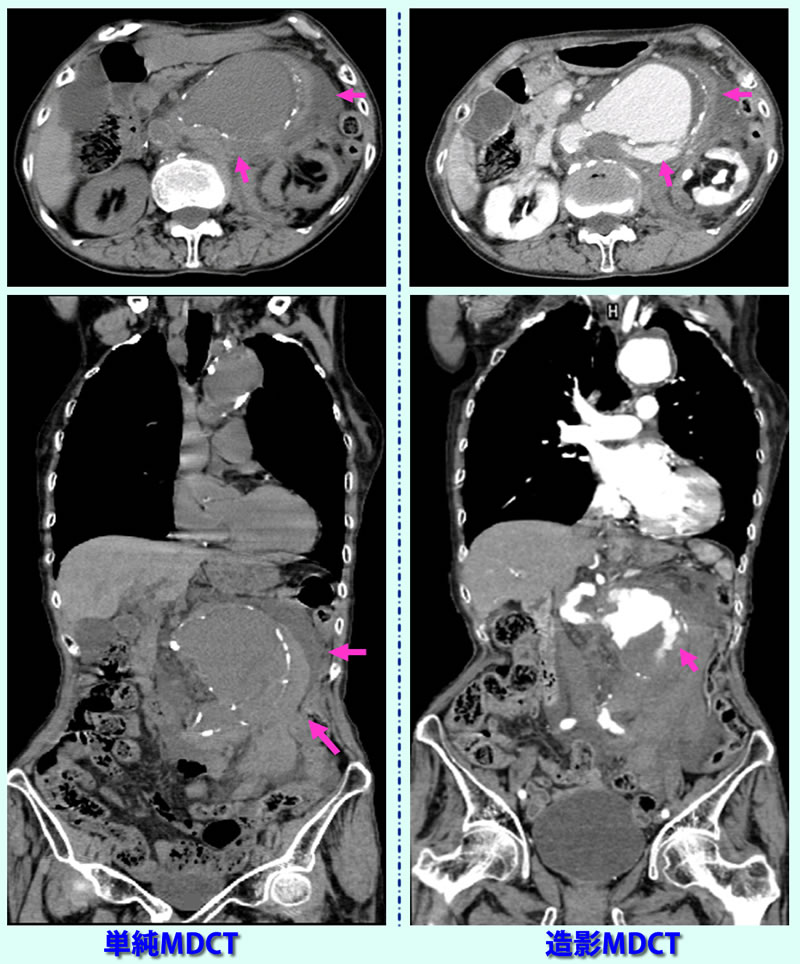

午後10時頃、突然、腹痛発症し、持続するため受診。単純CT検査(左側画像)で腹部動脈瘤破裂疑われ、造影MDCT検査実施(右側画像)。血管からの造影剤の漏出認め、大動脈破裂の確診.血管外科のある病院に救急搬送行ったが7時間後、他界。 大動脈瘤破裂